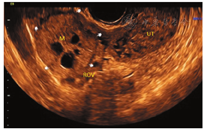

患者女,34岁,于顺产后43 d检查发现右侧卵巢囊实性肿块入院治疗。既往体健,生育史:孕4产2,曾流产2次。妇科查体:子宫正常大小,活动可,于右侧附件区可扪及一直径约5 cm肿块,活动可,界清,无明显压痛,左侧附件区未扪及明显肿块。辅助检查:CEA、CA199、CA125、AFP、卵巢癌相关抗原均为阴性。经阴道超声示:子宫体积正常(三径和约142 mm,宫颈厚28 mm,内膜厚约5.0 mm),宫壁未见明显肿块占位;右侧卵巢体积大、内可见一大小约49 mm×41 mm×39 mm的囊实性肿块,肿块边界清楚,形态规则,内部回声不均匀,可见多个囊性无回声区(较大者约13 mm×11 mm)(图1),能量多普勒示肿块内部及周边可见点条状血流信号(图2),脉冲多普勒(PW)示最高流速(Vmax)0.18 m/s,最低流速(Vmin)0.09 m/s,阻力指数(RI)0.50;子宫及左侧附件区未见明显异常回声。超声提示:①右侧卵巢内囊实性肿块;②子宫及左侧卵巢未见明显异常。进一步行超声造影成像示:增强早期时,右侧卵巢内肿块周边呈环状高增强,并早于子宫肌层增强(图3);内部实性部分呈不均匀等增强,并与子宫肌层同步增强;内部囊性部分无增强(图4)。造影剂消退时,肿块内部早于子宫肌层消退,而周边仍呈环状增强(图5),超声造影提示右卵巢肿块血供较丰富,表现"快进快退"。磁共振增强扫描提示:子宫右上方占位,考虑来源右卵巢性索间质肿瘤-颗粒细胞瘤可能,其他待排。术前拟诊"盆腔肿块性质待查",予行腹腔镜下右侧附件切除术,术中所见:右侧卵巢内见一肿瘤,直径约5 cm,呈囊实性,表面包膜完整,右侧输卵管攀附其上,外观正常;子宫正常大小,左侧卵巢及输卵管外观正常。术后病理镜下见肿瘤细胞弥漫性增生,呈片状、条索状,灶性腺样结构,部分区域可见大小不等的囊腔,核大小较一致,圆形或椭圆形,核仁可见,核分裂象约1~2个/10HPF,间质纤维组织及厚壁血管增生,黏液样变、灶性出血。免疫组化结果显示:Vimentin(+),CD10(+),ER(-),PR(-),CD34(血管+),EMA(-),P53(散在弱+),Ki67(灶性15%+)(图6)。结合免疫组化考虑卵巢性索-间质肿瘤,倾向卵巢间质瘤,送至复旦大学妇产医院会诊,诊断为右侧卵巢微囊性间质瘤。

卵巢MCST形态学表现上有完整的包膜,且实性肿块内部有特征性的微囊结构,这些在二维超声图像上有相应的表现,如本例患者卵巢MCST经阴道超声表现为卵巢内囊实性肿块,肿块边缘可见少量正常卵巢组织并与卵巢界线清楚,肿块边界清楚,形态规则,中央部可见多个规则的囊性无回声区(长径约10 mm)、透声好。彩色血流示肿块周边可见半环形血流信号,内部可见少许点状血流信号显示,频谱多谱勒显示为中等阻力。超声造影增强早期表现为包膜最先呈环状高增强(始增时间早于宫体),内部与宫体同步等增强,并由周围向中心增强,消退期表现为内部早于子宫肌层消退,而包膜仍呈环状持续高增强。